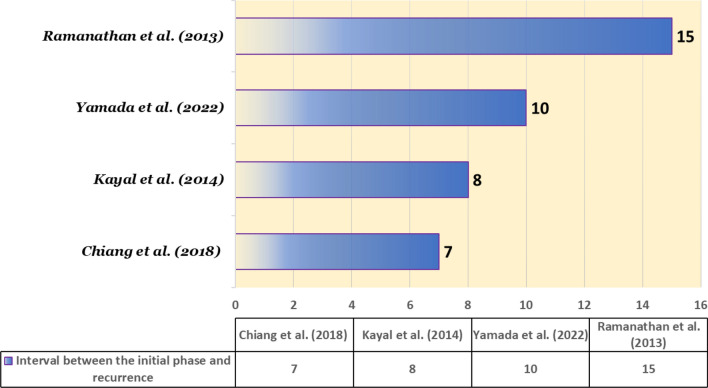

A study by Gong et al. showed that 82% of relapses occurred within the initial 2-year period [ref. 9]. Few cases have been reported to have a more than 5-year gap between the first and the last episode [ref. 23, ref. 24] (Fig. 5). However, in most cases, the severity of the disease in the relapse is less than in the initial phase [ref. 8, ref. 9, ref. 25]. In some cases, the relapse can be very severe [ref. 26].

Table 3 presents a comprehensive analysis of some late relapses of anti-NMDAR encephalitis.

Table 3: Late relapse of anti-NMDA receptor encephalitis in literature

| Study | Country | Sex | Age (years) | Late relapse | Prodrome | Symptoms in the recurrence | Treatment and outcome |

|---|---|---|---|---|---|---|---|

| Kayal et al. (2014) [ref. 27] | India | Female | 13 | 8 years | Subacute onset anti-epileptic drugs-resistant seizures; unusual behavior; and abnormal body movements | Dysgraphia, tremor of the right hand, seizures, agitation, and anxiety, with lack of response and verbal mutism, bruxism, dystonia, generalized rigidity, insomnia, and depression | IVMP, IVIG, and oral prednisoloneImprovement and relief of symptomsThe patient had amnesia, minor linguistic disintegration, and intermittent agitation |

| Yamada et al. (2022) [ref. 28] | Japan | Female | 13 | 10 years | Lack of sensation in the left hand, decreased level of consciousness, and seizures | Hypoesthesia on the right-side of the body, dysarthria, amusia, and seizures | IVMP and high-dose IVIGImprovement and relief of symptomsPositive outcomes |

| Chiang et al. (2018) [ref. 10] | US | Female | 33 | 7 years | Refractory epilepsy | Vomiting and abnormal behavior (due to recent cannabis consumption) | IVMP and rituximabNon-focal follow-up evaluationPositive outcomes |

| Ramanathan et al. (2013) [ref. 29] | Australia | Female | 31 | 15 years | Viral prodrome, generalized seizures, psychosis, and excited catatonia | Same as the initial phase | IVMP, immunoglobulin, plasma exchange, and rituximabNo long-term improvementPositive outcomes |

Prodrome (early sign and symptom); late relapse (interval between the initial phase and recurrence of disease). IVMP, intravenous methylprednisolone; IVIG, intravenous immunoglobulin